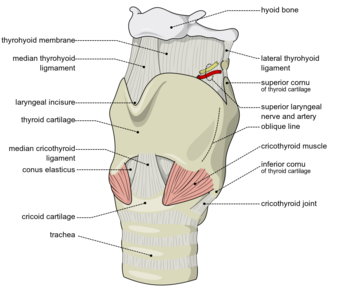

تشريح الحنجرة، منظر anterolateral | |

الحنجرة (بالإنجليزية : Larynx) هي الجزء الأمامي من العنق, عريضة من أعلى, مثلثة الشكل, وتتكون من عدة غضاريف تتحرك بوساطة عضلات مبطنة بغشاء مخاطي, يمتد في تجويفها الحبلان الصوتيان, حيث ينتج الصوت عن طريق الهواء المدفوع من الرئتين ليذبذب الأحبال الصوتية. ويحرس مدخل الحنجرة زائدة غضروفية تسمى لسان المزمار, له دور مع حركة الحنجرة عند الإبتلاع.